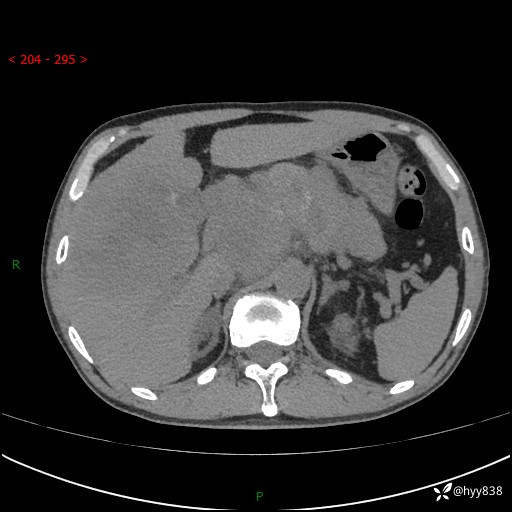

56岁/男,持续性干咳1周余,外院超声发现肝占位,少见病例---结果公布~

现病史:患者1周前无明显诱因出现刺激性干咳,伴食欲减退,无痰,无发热、头晕头痛、恶心呕吐、腹痛腹泻、胸闷喘气、厌油、巩膜黄染等不适,于当地诊所就诊并予以输液治疗,具体不详,患者诉干咳症状稍微好转,现患者为行进一步检查于当地第五人民医院就诊,肝脏彩超提示“肝占位性病变”,遂转入我院门诊就诊,经检查后门诊以“肝占位性病变”收入我科。 患者自起病以来精神、食欲如上述、睡眠一般,大小便正常,近半月内体重降低20余斤,体力无明显下降。

上腹部CT平扫+增强(两期)